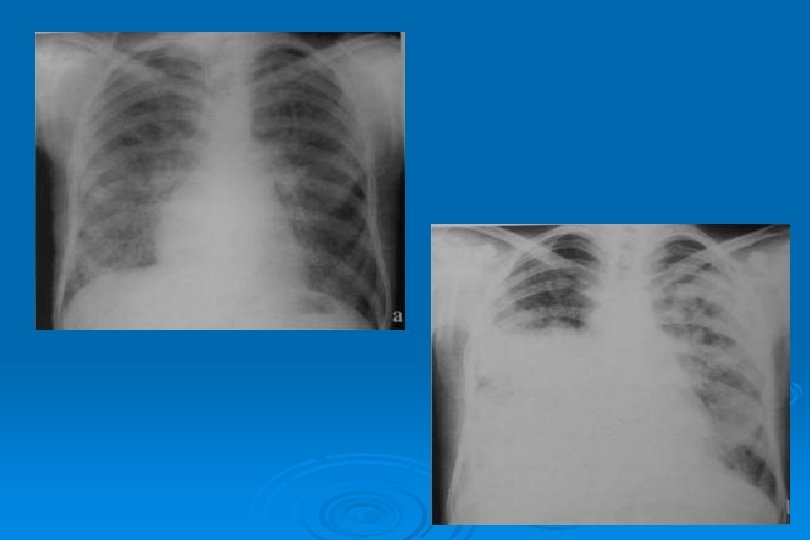

SİTOMEGALOVİRÜS • Birden fazla odakda, iki taraflı buzlu cam yoğunluğu ve konsolidasyon alanları • Milimetrik nodüller

İnfluenza Virüs Pnömonisi

VİRAL AC ENFEKSİYONLARI Toplum kökenli pnömonilerin % 25’i Ø Yaygın ya da dağınık infiltrasyon şeklinde olan bakteriyel pnömonilerden ayrımı çok zordur Ø Klinik bilgi verilmediğinde olgularda pnömoninin viral veya bakteriyel olduğunu tahmin etmek güçtür Ø Lober genişleme, mikroabseler, kavitasyon ve ampiyem bakteriyel pnömoniyi destekler Ø

VİRAL AC ENFEKSİYONLARI Ø Viral pnömoni damlacık enfeksiyonudur Ø Trakeit, bronşit ve bronşiolit tablosu ortaya çıkar Ø AC grafisinde hilustan perifere yayılım, asiner gölgeler ve yer peribronşial kalınlaşmalar saptanır

LOKALİZE VEYA YAYGIN HEMORAJİK ÖDEM Lokal olduğunda radyolojik görünümü segmenter veya lober pnömoniye benzer Ø Yaygın hemorajik ödem akut ve şiddetli viral pnömonide hızla ortaya çıkan bir tablodur Ø Perihiller perifere doğru azalan yaygın alveoler opasiteler görülür Ø Bazen plevral effüzyon olaya eşlik eder Ø İnfluenza virüsü en sık nedendir Ø